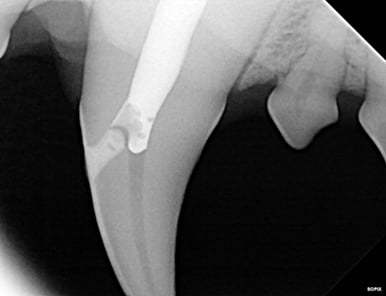

Below: Radiograph of 204 of the apex (tip of root). Beyond the wide pulp chamber, nothing significant is noted, yet studies show 43% of discolored teeth have no radiographic signs of problems, but have pulp necrosis and disease that leads to additional, potentially systemic issues.

%20-%20March%202024/Radiograph%20before%20RCT%20-%20apex.jpg?width=386&height=297&name=Radiograph%20before%20RCT%20-%20apex.jpg)

Below: Before RCT - Radiograph of 204 to aid in planning the access point

%20-%20March%202024/radiograph%20before%20RCT%20-%20access%20point.jpg?width=386&height=297&name=radiograph%20before%20RCT%20-%20access%20point.jpg)